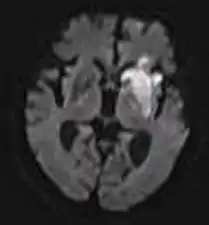

Le immagini pesate in diffusione (DWI, dall'inglese diffusion weighted imaging) evidenziano le variazioni della mobilità dei protoni dell'acqua in un tessuto biologico. In queste immagini, strutture con diffusione "normale" sono convenzionalmente rappresentate più scure, perché sostanzialmente il segnale di risonanza è più attenuato ("abbattuto"), mentre laddove la velocità di diffusione è minore ("ristretta"), come nell'ischemia per esempio, vengono rappresentate più chiare.

Rispetto alla RMN tradizionale la tecnica DWI si è dimostrata più sensibile nel valutare in acuto l'entità dei danni da edema dovuto ad un episodio cerebrovascolare, anche prima della TC.

La DWI è anche sensibile ad altre alterazioni edemigene e anche di tipo tumorale anche in altri tessuti, come il fegato, per esempio. Il substrato biologico che giustifichi la positività in DWI in queste diverse realtà patologiche non è ancora stato chiarito. Sembra in relazione all'ipercellularità di alcuni tumori. Per quanto riguarda l'ictus cerebrale è correlato all'insulto assonale: l'assone perde infatti la propria morfologia, formandosi lungo il suo decorso delle varicosità (assone a corona di rosario) che ben correlano con la restrizione della diffusione delle molecole d'acqua. Tale dato è confermato anche da modelli animali e matematici.[1] [2]